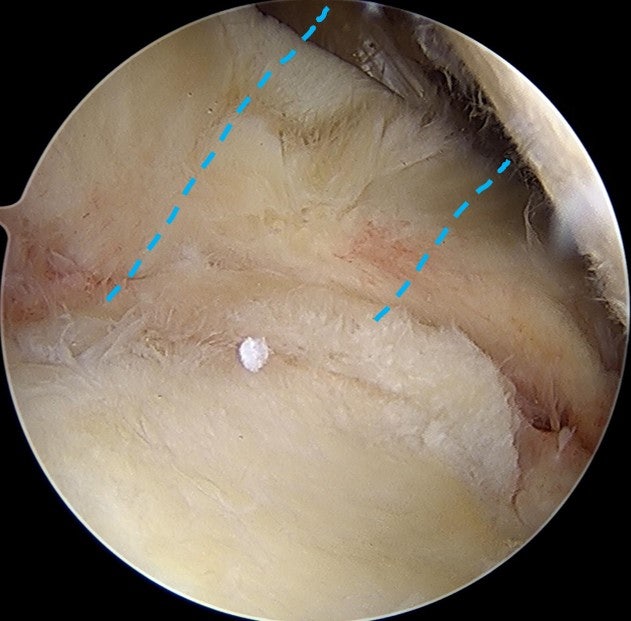

수술 후 3개월차에 다시 MRI 영상을 확인해 보았습니다.

광범위한 회전근개 파열이 있는 경우 완전히 해부학적으로 복원되지 않는 경우가 있습니다. 할 수 있는 만큼만 봉합을 한 경우 회전근개의 부착 부위가 원래의 해부학적으로 부착하는 것보다 적어지기 때문에 재파열이 발생할 가능성이 있고 회전근개의 기능의 회복도 잘 되지 않을 가능성이 많습니다. 이러한 경우 인조인대를 이용하여 보강술을 해주면 원래의 모양대로 해부학적인 복원이 가능하게 됩니다. 인조인대를 이용한 보강술을 술기가 복잡하고 어렵게 때문에 이러한 수술을 하는 병원이 많지는 않습니다. 모든 수술의 원칙은 손상된 조직의 해부학적인 복원입니다. 이를 할 수 없는 경우라도 최대한 근접하게 복원하는 것이 좋은 결과를 위해 매우 중요하다고 생각합니다. 환자분은 현재는 거의 정상적으로 활동하고 계시며 매우 만족하며 생활하신다고 합니다. 해부학적으로 복원 불가한 광범위 회전근개파열도 정상으로 회복될 수 있습니다!!!